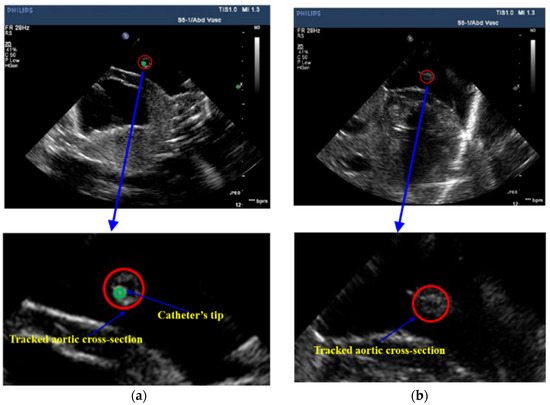

After tracking aortic cross-sections in US images, threshold technology is applied to obtain those pixels whose intensities are higher than 220 inside the aortic cross-section. The centroid of those pixels is the detected position of the cross-section of the catheter. In Figure 7, the red circle represents the tracked aortic cross-section and the green point is the located tip of catheter. Based on the positions of the catheter’s tip, the 3D trajectory of the catheter is acquired. Figure 8 shows two trajectories of the catheter, including an automatic trajectory of the catheter from our multi-feature particle filter tracking method and a 3D trajectory from the manually delineative catheter’s tip. The distance between the manual trajectory and automatic trajectory using multi-feature particle filter tracking method is 1.48 mm.

Figure 7. Tracking result of aortic cross-section and catheter’s tip in US images, (a) the US image which contains the catheter’s tip; (b) the US image which does not contain the catheter’s tip.